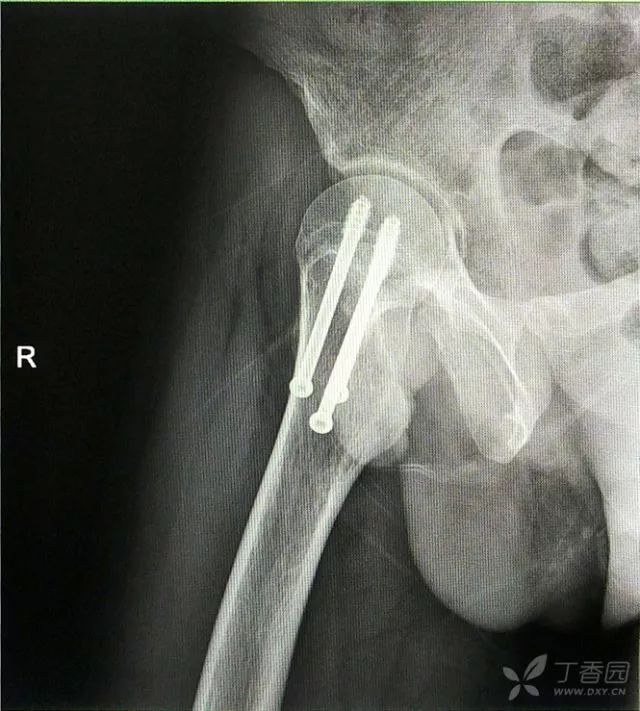

1. 对于难复性股骨颈骨折,术前应做好切开复位的准备,该患者复位三次都不太满意。

2. 倒数第二次的复位仍是欠缺一点

3. 再努力一把就基本成了